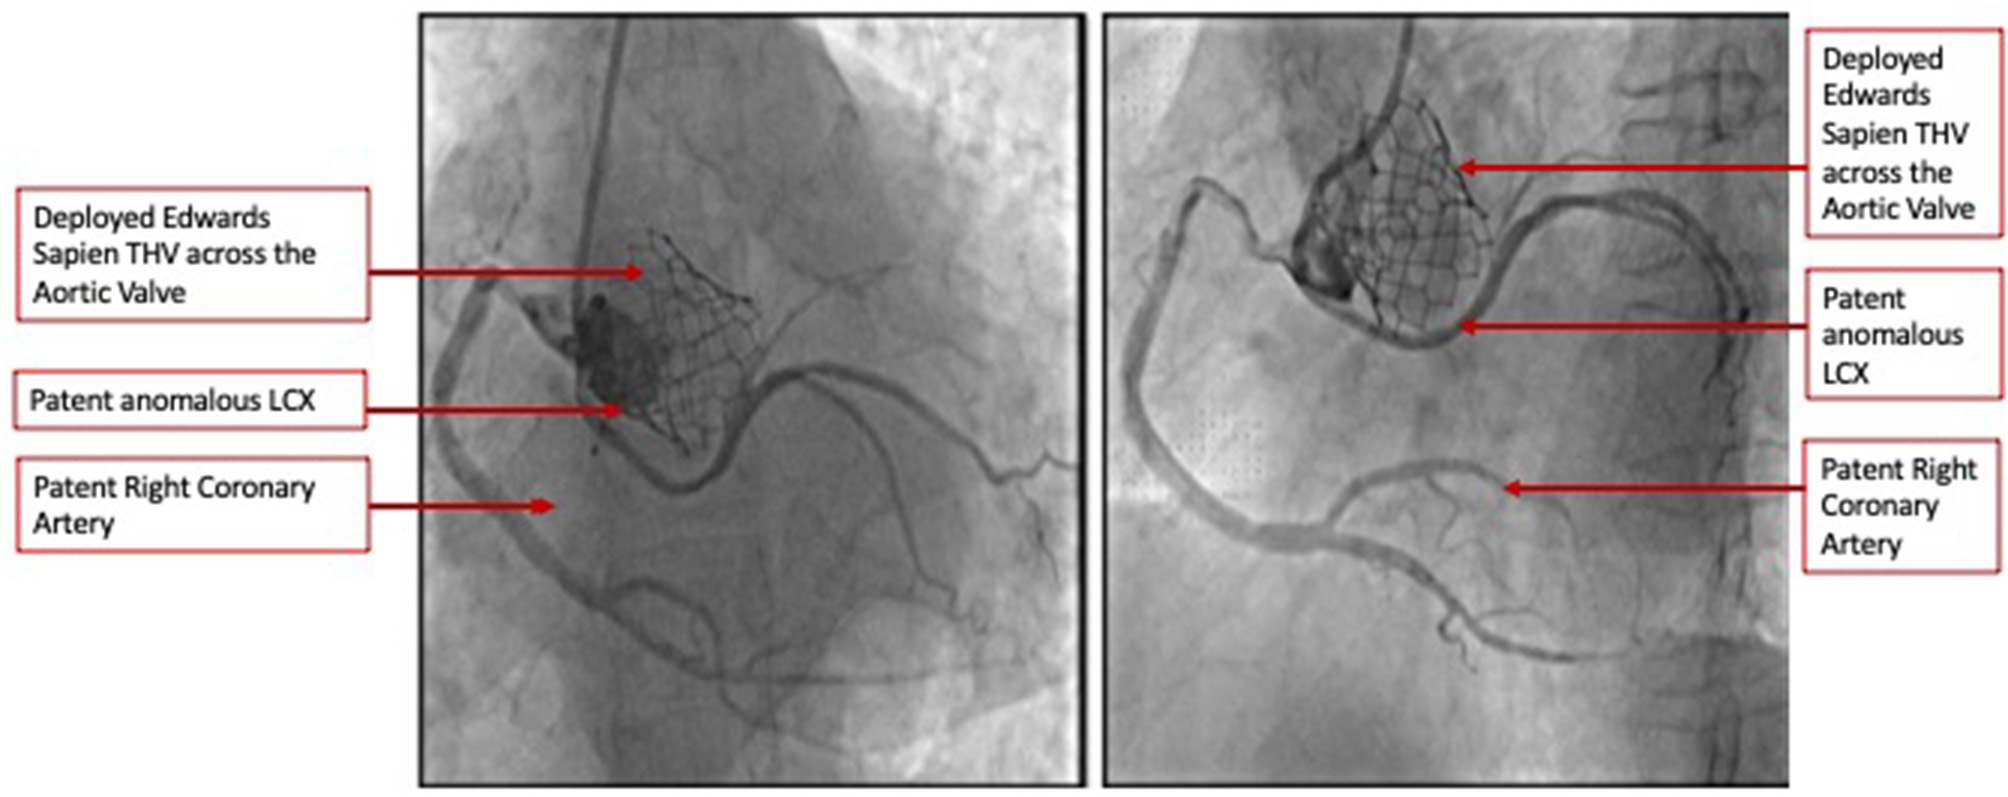

Figure 3

Selective coronary angiography demonstrating widely patent coronary arteries including the anomalous LCX in two orthogonal views.